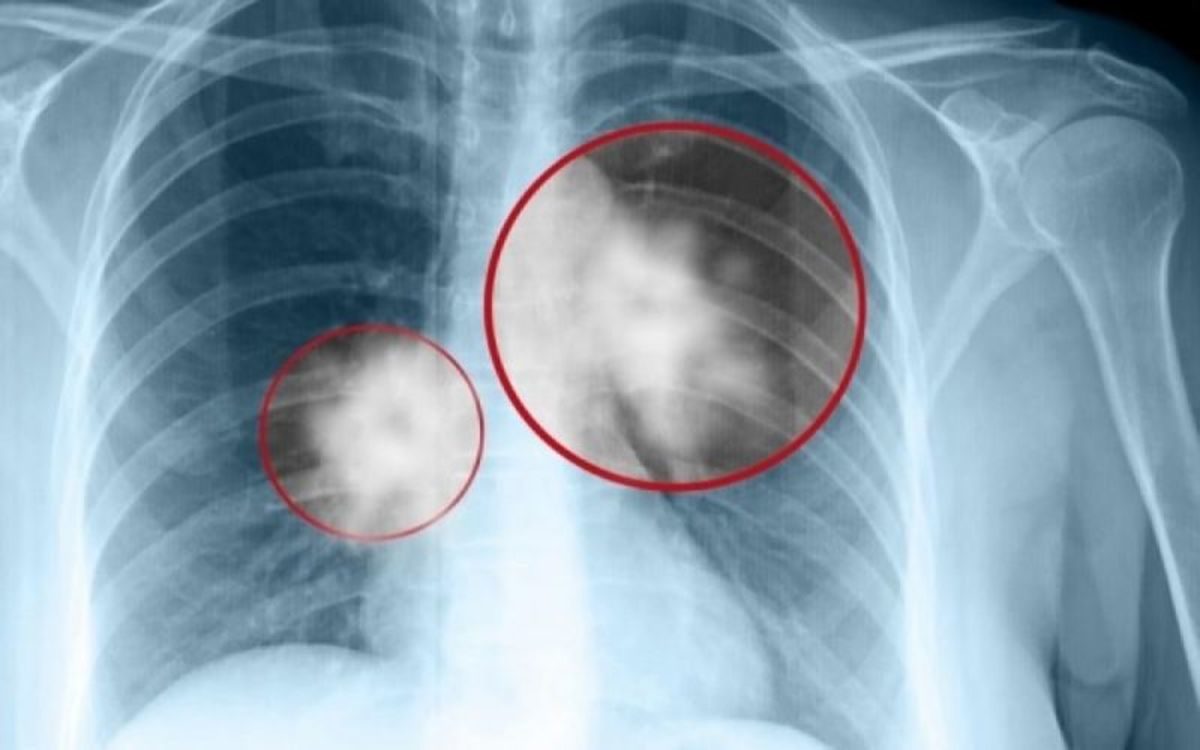

«Σύμφωνα με τον Παγκόσμιο Οργανισμό Υγείας από τα 7,6 εκατομμύρια θανάτους κάθε χρόνο, λόγω καρκίνου σ’ όλον τον κόσμο, οι 1.370.000 οφείλονται σε καρκίνο του πνεύμονα. Η νόσος αναπτύσσεται κυρίως σε άτομα άνω των 60 ετών και προκαλείται από την ανεξέλεγκτη ανάπτυξη ανώμαλων κυττάρων, συνήθως κατά μήκος των αναπνευστικών οδών. Τα μη φυσιολογικά κύτταρα δεν αναπτύσσονται σε υγιή ιστό, διαιρούνται γρήγορα σχηματίζοντας όγκους, οι οποίοι σταδιακά μεγαλώνουν και πολλαπλασιάζονται, εμποδίζοντας την επαρκή παροχή οξυγόνου στο αίμα», μας εξηγεί ο χειρουργός θώρακος και καρδιάς Δρ. Γεώργιος Πολυχρονόπουλος (www.gpolychronopoulos.gr), επισημαίνοντας ότι απαιτούνται πολλά χρόνια μέχρι τα συμπτώματα να γίνουν αντιληπτά από τον ασθενή, με αποτέλεσμα να καθυστερεί η διάγνωση και η θεραπεία της νόσου.

Τα συνδυασμένα αποτελέσματα φανέρωσαν στους ερευνητές ότι η μέση επιβίωση μετά από χειρουργική επέμβαση καρκίνου του πνεύμονα ασθενών με καρκίνο σταδίου Ι (αρχικό) ήταν 6,7 χρόνια, σχεδόν 2 χρόνια περισσότερο από ό,τι το ποσοστό επιβίωσης αναφοράς των 5 ετών. Επιπλέον, η μελέτη έδειξε ότι το ποσοστό 5ετούς επιβίωσης για επιλεγμένους ηλικιωμένους ασθενείς με προχωρημένο καρκίνο του πνεύμονα που έλαβαν θεραπεία με χειρουργική επέμβαση ήταν 29,9% για το στάδιο ΙΙΙ και 26,7% για το στάδιο IV.